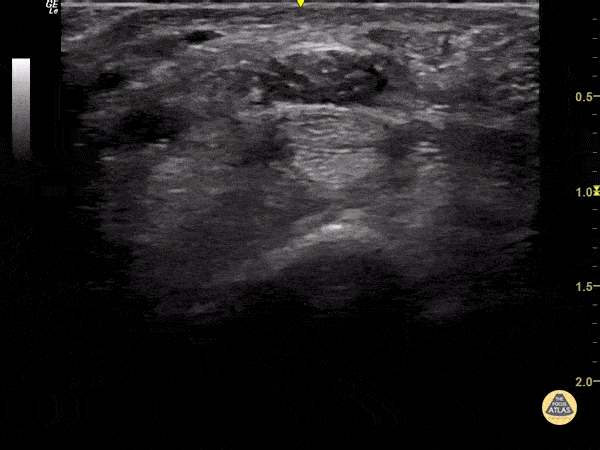

55 y/o female with recurrent carpal tunnel symptoms not improved with conservative management. Benefits of US guidance include vessel avoidance, and needle placement for surrounding median nerve with steroid solution. Dr. Magner